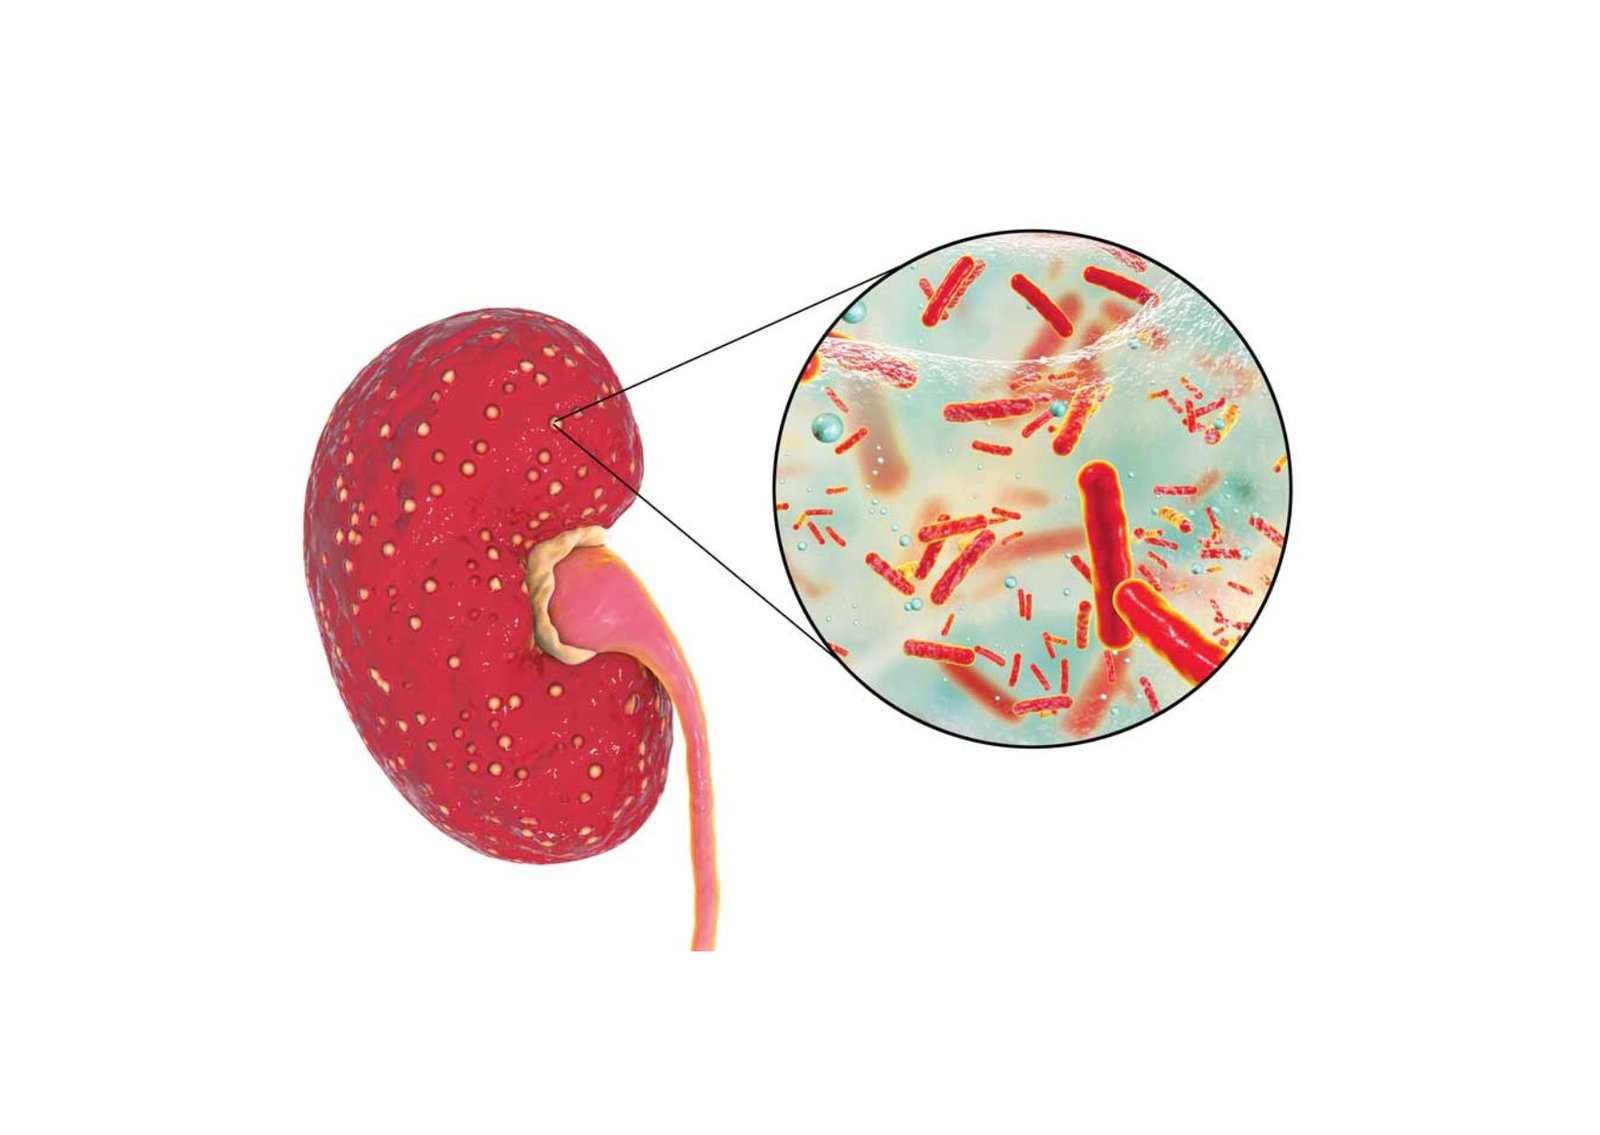

A complicated urinary tract infection indicates that underlying anatomical, functional, or systemic factors are actively compromising the body’s ability to clear the bacterial pathogen. In these elevated risk scenarios, the infection can rapidly ascend from the bladder, travel upward through the ureters, and aggressively invade the renal parenchyma.

Acute Pyelonephritis: When a patient presents with severe unilateral flank pain, systemic chills, and a high fever, the bacterial infection has likely successfully reached the upper urinary tract.

An ultrasound is immediately ordered to detect renal abscesses, evaluate localized areas of severe tissue inflammation, and rule out any physical blockages causing infected urine to back up into the kidneys.

Acute Pyelonephritis | Global physical enlargement of the affected kidney, a loss of the normal visual distinction between the cortex and the medulla, and localized hypoechoic (dark) regions indicating severe tissue edema. | Confirms the bacterial infection has successfully ascended from the bladder and actively invaded the functional renal tissue. |

Renal or Perirenal Abscess | A clearly defined, complex cystic structure featuring thick, irregular walls and internal fluid debris, often located within the renal parenchyma or the immediately adjacent fatty tissue. | Identifies a dangerous, localized collection of infected pus that typically requires immediate intravenous antibiotics or targeted surgical drainage. |